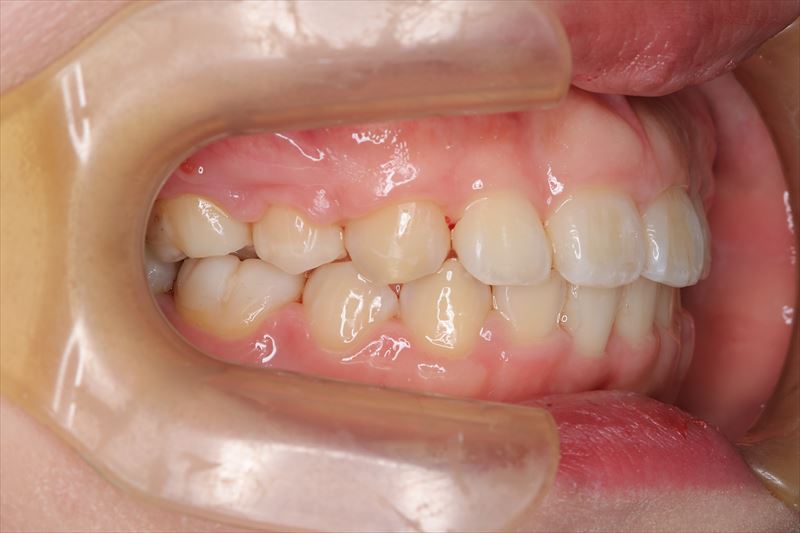

治療後

- 口唇の突出を気にされて来院いたしました。Eラインより口唇の突出、オトガイ部の緊張を認めました。アンカースクリューを用いて前歯の牽引を行うことによって良好な側貌となりました。治療途中で遠方に引っ越されたため来院が困難となり治療期間が延びてしまいましたが、患者様のご協力もあり無事に治療を終えることができました。